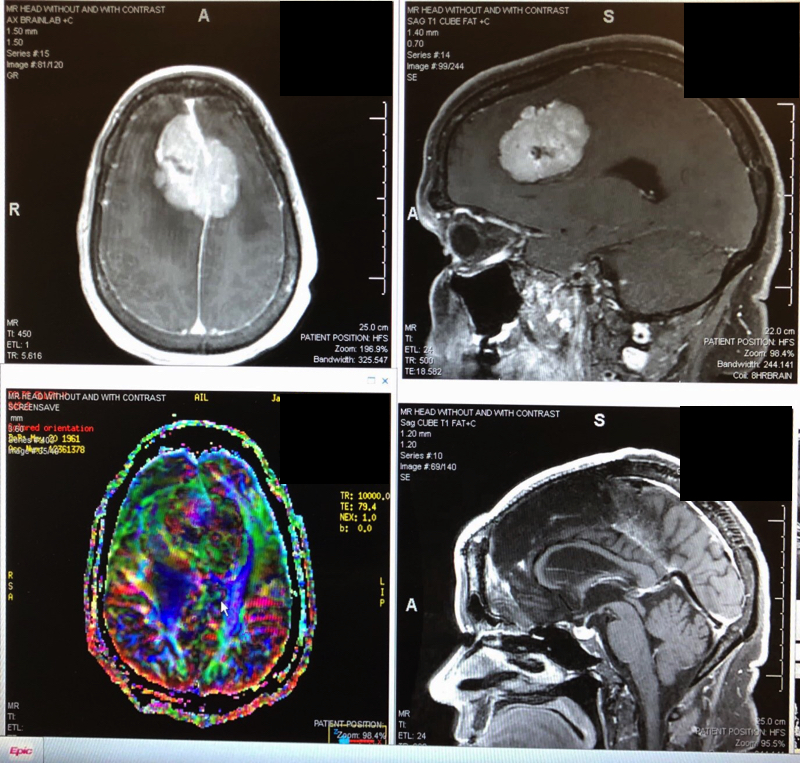

Top: brain tumor before surgery. Bottom: after stereotactic radiosurgery.